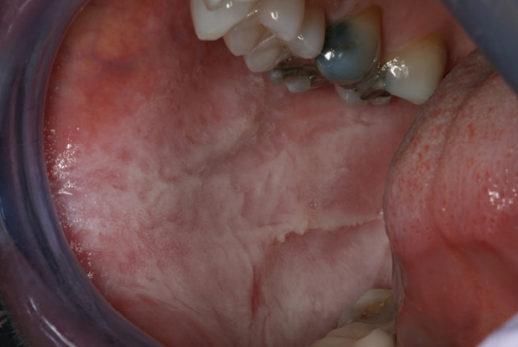

Leucoedema